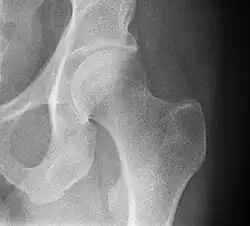

![X-ray of the hip, with measurements used in X-ray of hip dysplasia in adults.[36]](./_assets_/Iliopectineal_line%252C_ilioischial_line%252C_tear_drop%252C_acetabular_fossa%252C_and_anterior_and_posterior_wall_of_the_acetabulumi.jpg)